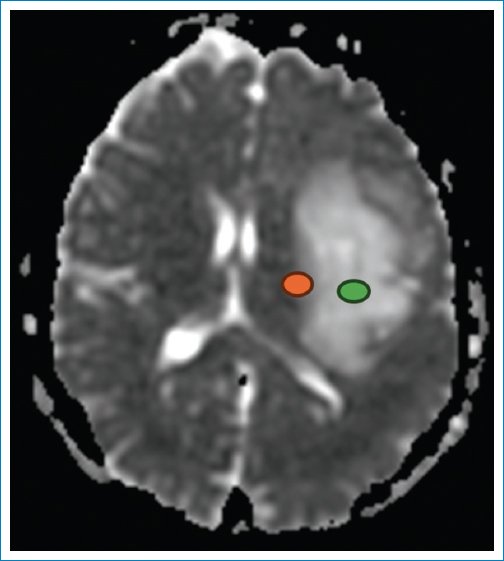

La secuencia de difusión aporta un ADC diferente en la periferia de la neoplasia (0,69 × 10–3 mm2/s) (Fig. 5), que es bajo, indicando mayor celularidad, y es alto en el centro (1,75 × 10–3 mm2/s)5,6. Este último valor refuerza la hipótesis de un IDHm y no codeleción de 1p/19q. Lo mismo ocurre con los valores obtenidos en la medición de la anisotropía fraccional, la difusión paralela y la difusión perpendicular79 (Fig. 6).

Figura 5. ADC = 0,69 × 10–3 mm2/s (en naranja) y 1,75 × 10–3 mm2/s (en verde).